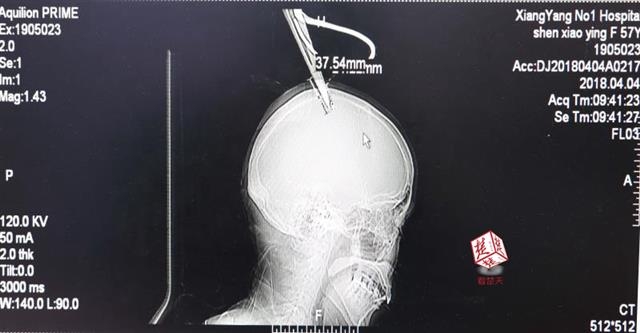

醫生檢查發現,剪刀刀尖斜嵌在沈某顱骨里,離腦髓只有兩三毫米。所幸是斜著插進去,如果是垂直刺入,很有可能造成癱瘓。

4月4日清晨,襄陽市樊城區太平店鎮57歲的農村婦女沈某,在采摘香椿嫩芽時,綁在竹桿上的剪刀因竹子腐朽不慎折斷,剪刀斜插入頭顱。經過及時搶救,目前脫離生命危險。

醫生檢查發現,剪刀刀尖斜嵌在沈某顱骨里,離腦髓只有兩三毫米。所幸是斜著插進去,如果是垂直刺入,很有可能造成癱瘓。最終經過手術,剪刀被取出,沈某目前仍在ICU進一步觀察。